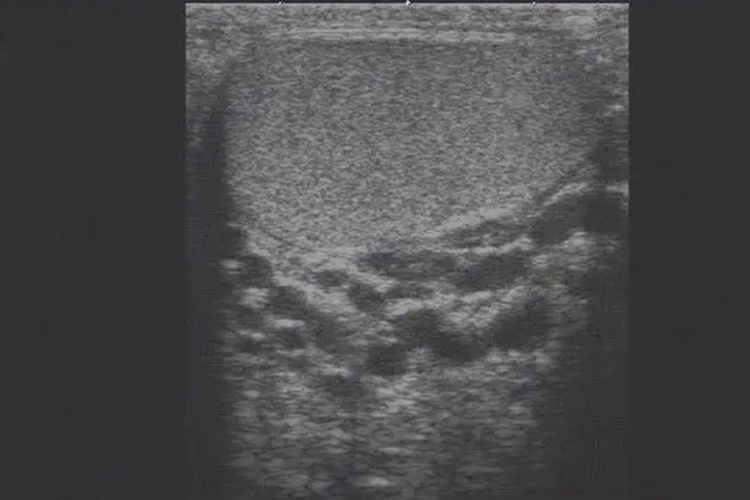

精索静脉曲张是一种血管性疾病,超声可表现为睾丸后上方及阴囊根部探及迂曲的管状结构,官腔内呈无回声或云雾状的低回声。

精索静脉曲张超声可表现为睾丸后上方及阴囊根部探及迂曲的管状结构,部分区域可呈“蜂窝样”改变,管壁薄而清晰,官腔内呈无回声或云雾状的低回声,静脉最大内径超过2mm,站立或Valsalva试验时静脉内径增加,血流淤滞加重或出现持续反流。